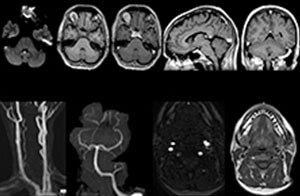

Klinische Fallbeispiele

„Für die routinemäßige, kontrastmittelfreie Untersuchung der Brust- und Halswirbelsäule führen wir zum Beispiel eine mDIXON T2-TSE-Sequenz durch, die uns zwei Ergebnisse liefert: die T2-gewichteten Bilder auf Fett- und Wasserbasis sowie die sagittalen T2-gewichteten Bilder auf reiner Wasserbasis. Anschließend erfolgt noch eine axiale Gradientenecho-Untersuchung.“

Routineuntersuchung der Halswirbelsäule